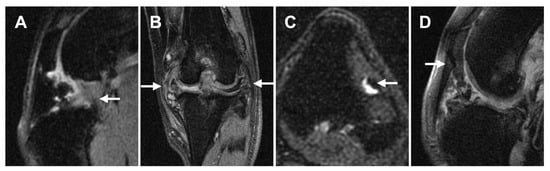

3.2.2. Ligament/Tendon Lesions

3.2.3. Synovial Effusion and Membrane Thickening

3.2.4. Subchondral Bone Lesions

3.2.5. Meniscal and Cartilage Lesions